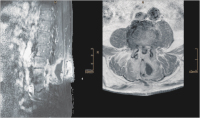

LWS

Abbildung 2: Kernspintomographische Aufnahmen der LWS (SPIR mit Kontrastmittel, sagittal geschichtet und in T 1 mit Kontrastmittel, horizontal geschichtet): Nachweis entzündlicher Veränderungen in LWK 3 und LWK 4 links paramedian.